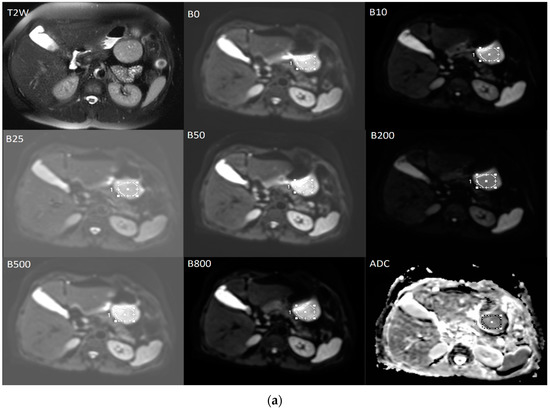

The diffusion weighted images were analyzed by a radiologist with 6 years of experience. T2-weighted images were used to help to determining the localization of the tumor more clearly and avoid necrotic areas (Figure 6). On diffusion-weighted images for b = 0, ROI were positioned within the solid tumor region, on three contiguous axial sections at the place of the largest tumor diameter and then automatically copied to all higher b-values parametric maps. Quantitative ADC maps were calculated on voxel-by-voxel basis on the commercial workstation by using the mono-exponential model for the combination of b = 0 and b = 800 [15].

Figure 6.

The averaged signal intensity decay and representative IVIM DW images. T2-weighted image in axial view is used for the precise localization of the tumor. DWI with multiple b-values and ROIs (a) followed by signal attenuation curve (b) where true diffusion coefficient (D slow), pseudo-diffusion coefficient (D fast) and perfusion fraction (f) were calculated based on the bi-exponential model.

The data for IVIM parameters: true diffusion coefficient (D slow), pseudo-diffusion coefficient (D fast), and perfusion fraction (f) were calculated based on the bi-exponential model by using the MITK Diffusion software, after fitting the signal values from manually located ROIs [15].

The final values of D slow, D fast, f, and the ADC for b = 0 and 800 s/mm² were calculated by averaging the three measurements (Figure 6) [15].